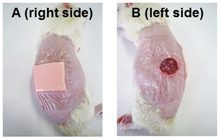

- Preparation of paraffin and frozen tissue sections in different sizes

- Preparation of sections from chemical and natural tissue scaffolds

- Examination of cell placement on tissue scaffolds with SEM microscopy

On the other hand, in cutting-edge sciences such as tissue engineering, the use of up-to-date techniques for section preparation and cell tracking and engineered tissue structure has contributed significantly to the development of new studies.